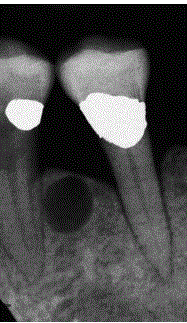

Befunde dieses RÖ-Bild

Panoramaschichtaufnahme. Zystischer Prozess im Unterkiefer links im Bereich der Schaltlücke in regio 36 ohne Lagebeziehung zum Zahnbestand.

Histologie: radikuläre Zyste. Diagnose: Residualzyste [nach Zahn- Extraktion]

Panoramaschichtaufnahme.

Zystischer Prozess im Unterkiefer links mit

Lagebeziehung zum wurzelgefüllten Zahn 37.

Histologie: radikuläre Zyste